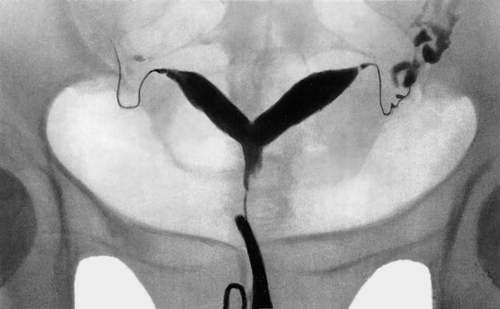

Перегородка в матке: полное руководство по диагностике и лечению аномалии

Обнаружили перегородку в матке и беспокоитесь о будущем здоровье и беременности? Наша статья подробно объясняет причины, симптомы и современные методы лечения этой врожденной аномалии, чтобы вы могли принять…

Седловидная матка: от диагностики до успешной беременности и родов

Диагноз седловидная матка вызывает много вопросов о возможности забеременеть и выносить ребенка. В статье подробно разбираем причины аномалии, современные методы диагностики, риски и особенности ведения…

Двурогая матка: полное руководство по жизни, беременности и лечению

Узнав о диагнозе двурогая матка, женщина ищет исчерпывающую информацию о влиянии аномалии на здоровье и возможность стать матерью. В статье разбираем причины, симптомы, современные методы диагностики и…